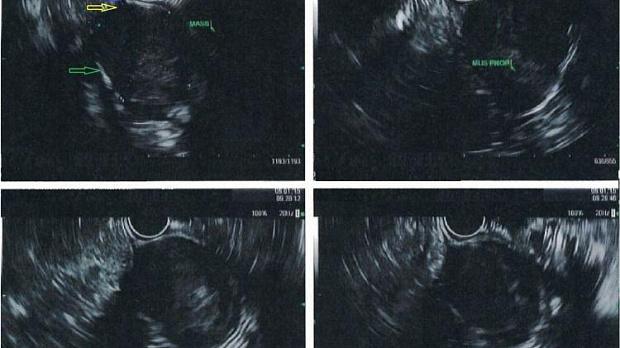

Эндосонография диагностическая методика, высокотехнологическое исследование, одновременно сочетающее в себе возможности эндоскопической и ультразвуковой диагностики.

Для исследования используют гибкий эндоскоп с видеокамерой и ультразвуковым датчиком. Его можно ввести в пищевод, желудок, двенадцатиперстную, прямую, толстую кишку, а также в дыхательные пути. Во время обычного ультразвукового исследования через кожу, когда нужно осмотреть орган, который находится глубоко, страдает четкость изображения. Эндосонография решает эту проблему. При помощи эндоскопа УЗ-датчик подводят максимально близко к исследуемому образованию. Во время исследования врач может провести тонкоигольную биопсию подозрительного образования. Использование в приборе очень высоких частот ультразвука (5,0; 7,5; 12 и 20 МГц) обеспечивает высокое качество изображения с разрешающей способностью менее 1 мм, недоступное другим методам исследования, таким как обычное ультразвуковое исследование, компьютерная и магнитно-резонансная томография, эндоскопическая холангиопанкреатикография. При этом эндосонография не сопряжена с риском рентгенологического облучения персонала и пациента, отсутствует опасность возникновения осложнений, свойственных ЭРХПГ.

Какое оборудование используется?

Существует два различных типа эхо-эндоскопов по типу сканирования ультразвуковыми датчиками:

• радиального - перпендикулярны оси эндоскопа - сканируют 360 градусов - диагностический

• конвексного - параллельно оси эндоскопа - сканируют примерно 100 градусов - имеет специальный "инструментальный" канал

Радиальное сканирование позволяет получить панорамное изображение (360°), перпендикулярное оси эндоскопа. Это наиболее ранние и самые распространенные модели эхо-эндоскопов, используются они только в диагностических целях.

Эхоэндоскопы конвексного типа сканирования введены в клиническую практику с 1990-х годов и позволяют получать 100° секторное ультразвуковое изображение, параллельное оси эндоскопа. Использование аппаратов данного типа, оснащенных инструментальным каналом, позволяет проводить пункционную биопсию под ЭСГ-контролем (ЭСГ-ПБ). Комплектация эхосканеров допплеровским и соно-эластографическими блоками значительно расширяет диагностические и лечебные возможности исследования.